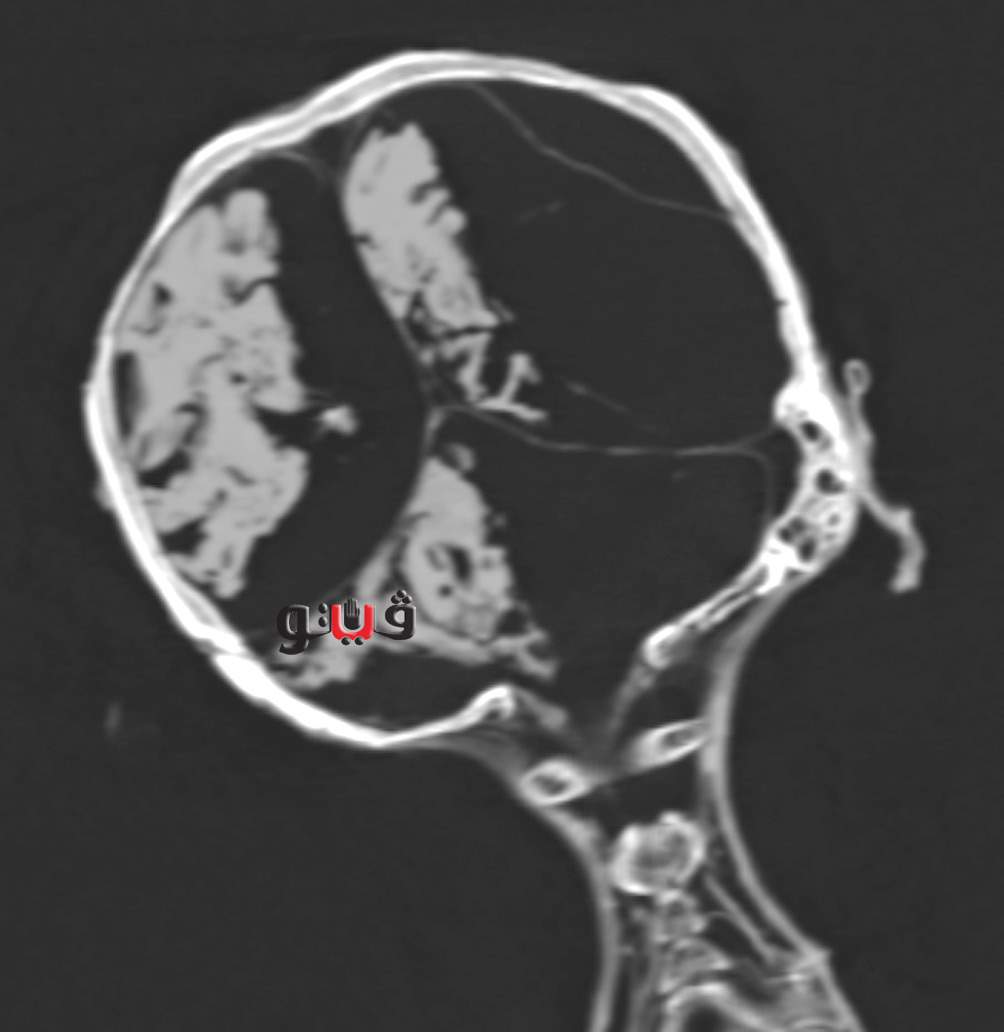

وأظهرت صور فحص الأشعة المقطعية ان المحنطين لم يستخرجوا مخ المومياء حيث لا يزال يرى المخ بداخل تجويف الجمجمة و لكنه يميل إلى الجانب الأيمن و ذلك لوضعية الجسد على هذا الجانب عند الموت و بعد التحنيط.